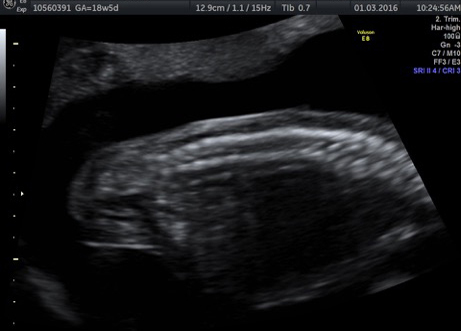

LUTO often is diagnosed by routine ultrasound in the second trimester of pregnancy. If the condition is suspected, other tests, including fetal MRI and echocardiogram, may be needed.